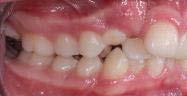

En las fotografías intraorales (Figura 3) observamos una clase II molar bilateral, clase II canina derecha, clase III canina izquierda, apiñamiento severo superior y moderado inferior, presencia de mordida abierta anterior y posterior a nivel de premolares (Figura 4), forma de arco triangular en la arcada superior y forma de arco oval en inferior, ausencia del OD 46 y presencia de un diente supernumerario.

De frente (Figura 7) presenta líneas medias dentales no coincidentes, 6 mm overjet, 10% overbite, relación molar y canina clase II bilateral. Las oclusales (Figura 8) la arcada superior de forma triangular, presencia de OD 53 y apiñamiento severo, la arcada inferior de forma cuadrada con segundos molares en erupción y apiñamiento moderado.